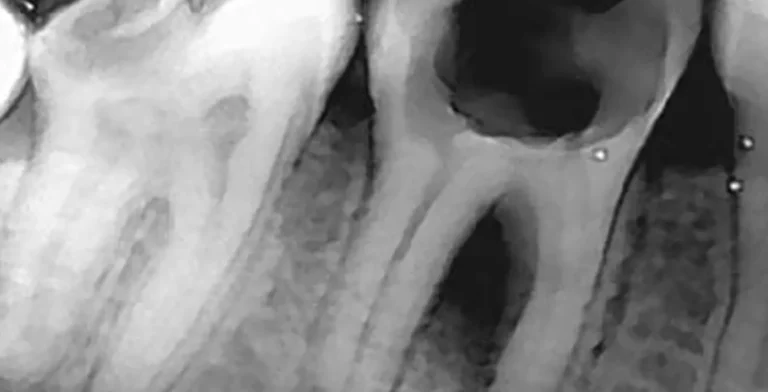

endo-ba04-before-treatment-vitrin-clinic endo-ba04-after-treatment-vitrin-clinic

endo-ba03-before-treatment-vitrin-clinic endo-ba03-after-treatment-vitrin-clinic

endo-ba02-after-treatment-vitrin-clinic endo-ba02-before-treatment-vitrin-clinic

endo-ba01-after-treatment-vitrin-clinic endo-ba01-before-treatment-vitrin-clinic